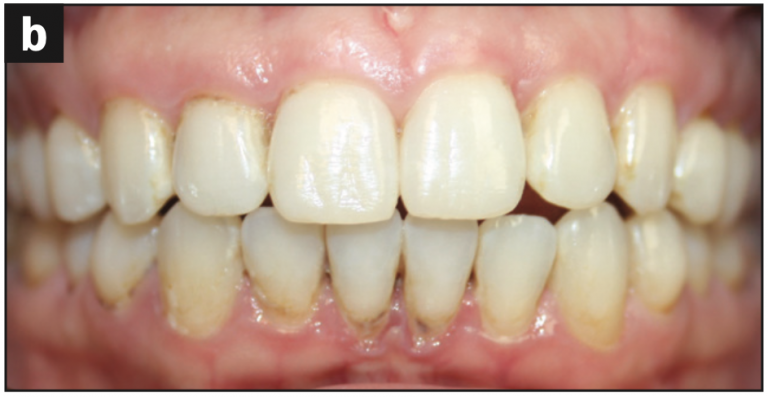

Intraoral images were captured, focusing on three surfaces of each tooth: buccal, occlusal/incisal, and lingual surfaces. The following issues were identified:

- Abfraction with decay (Figures 2a and 2b)

- Abfraction lesions (Figures 2c and 2d)